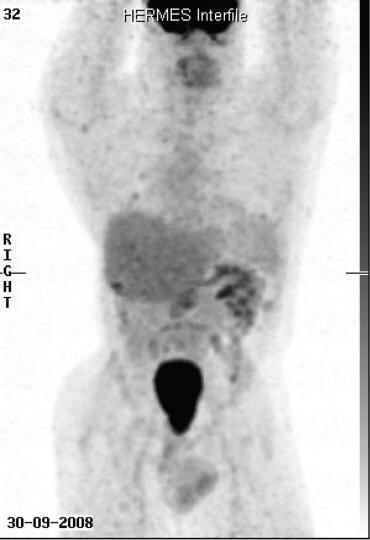

WilmsTumor In A 37-Year-Old - Researchgate.net

Wilms’ Tumor in a 37-Year-Old Abstract Wilms’ tumor is rare in adults. Though the approach to diagnosis to alternative treatment for adults where initial chemothera-py fails or the disease recurs. While the concern in children ... Return Doc